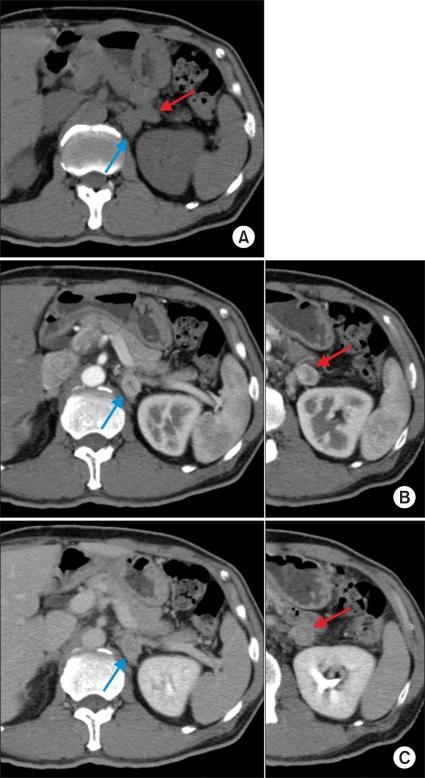

A 63-year-old male patient visited our hospital with a right incidental renal tumor, which was found by ultrasonography for the follow-up study of chronic hepatitis B virus infection and diabetes mellitus. Consecutive computed tomography revealed a right renal tumor and two left adrenal tumors. Further systemic imaging study and hormonal examination suggested one right renal cell carcinoma and left adrenal metastases. We performed right nephrectomy and left adrenalectomy. The pathological diagnoses of all resected tumors were renal cell carcinoma. The patient has been in good health without any recurrence for 12 months since the operation. In patients with renal cell carcinoma, contralateral adrenal metastasis is usually associated with multiple metastases to other organs. There are a few cases of solitary and synchronous contralateral adrenal metastasis in the English literature. To our knowledge, this is the first report of a case of renal cell carcinoma with double synchronous contralateral adrenal metastases.

一名63岁男性患者因右肾偶然发现的肿瘤前来我院就诊,该肿瘤是在对慢性乙型肝炎病毒感染和糖尿病进行超声随访检查时发现的。连续的计算机断层扫描显示右肾有一个肿瘤以及两个左肾上腺肿瘤。进一步的全身影像学检查和激素检查提示为右肾细胞癌伴左肾上腺转移。我们实施了右肾切除术和左肾上腺切除术。所有切除肿瘤的病理诊断均为肾细胞癌。自手术以来,患者已健康存活12个月,无任何复发迹象。在肾细胞癌患者中,对侧肾上腺转移通常与其他器官的多发转移相关。英文文献中仅有少数孤立性和同步性对侧肾上腺转移的病例报道。据我们所知,这是首例双发性同步对侧肾上腺转移肾细胞癌病例的报告。